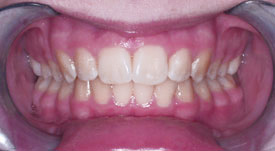

Crossbite

Crowding Front

Crowding Lower

Crowding Upper

Midlines

Narrow Upper Arch

Openbite

Overbite Front

Overbite Side

Protrusion

Spacing

Underbite